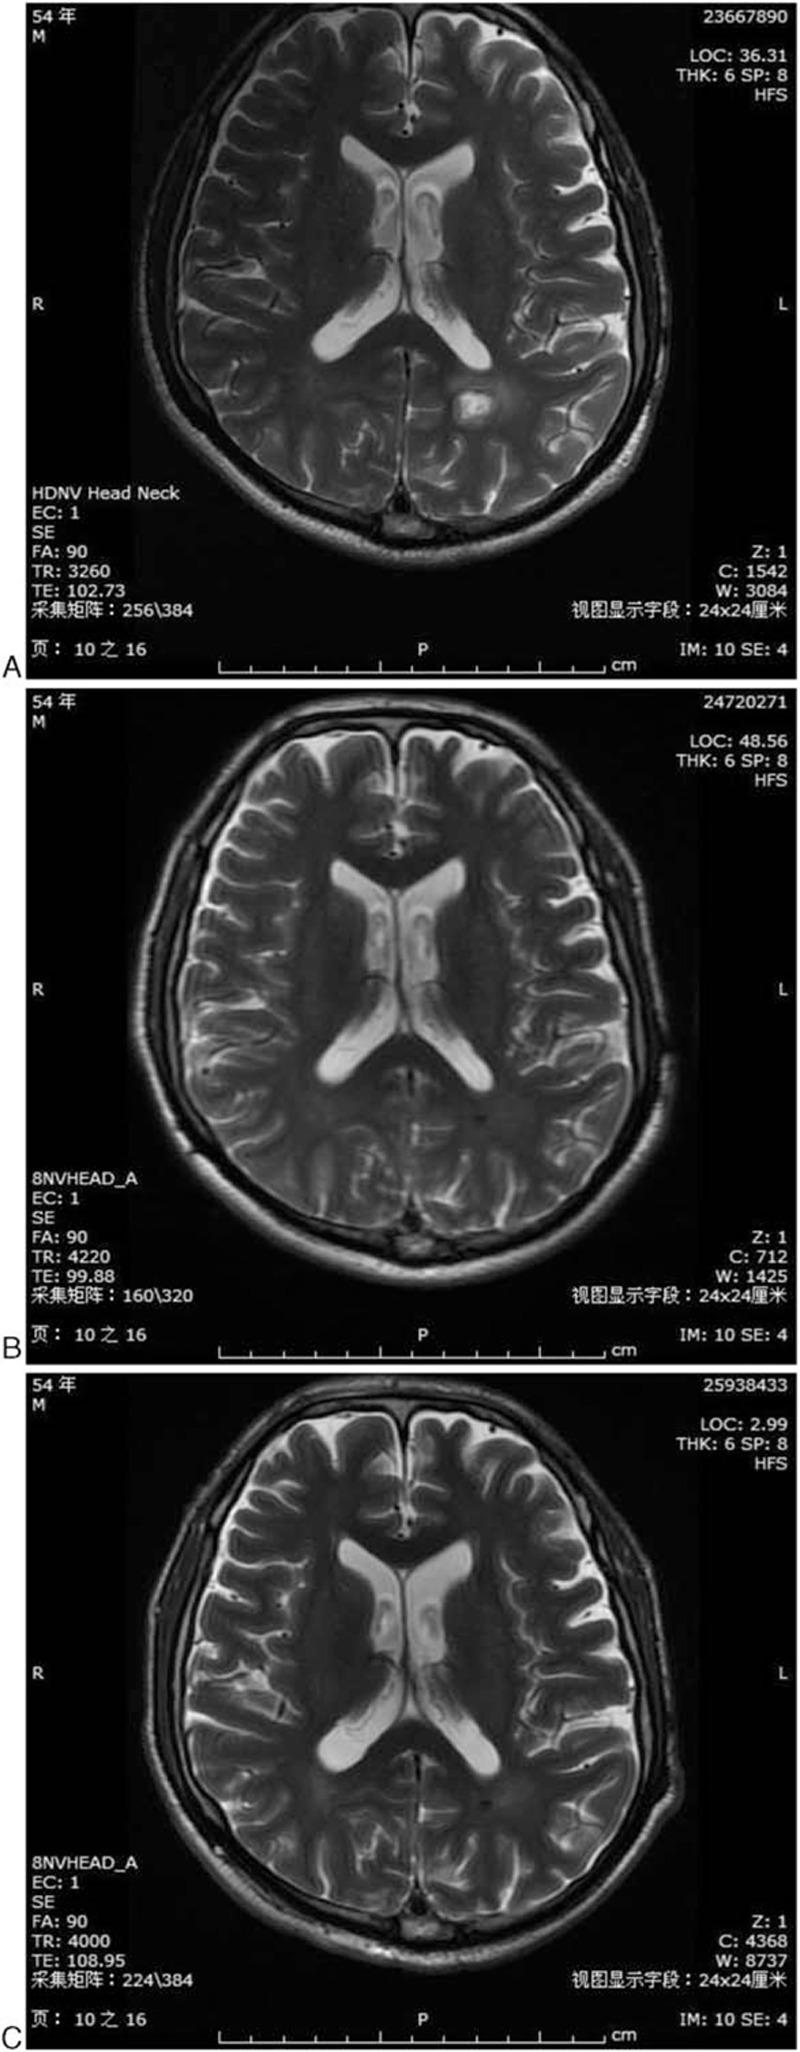

He benefited from administration of first-line chemotherapy of pemetrexed/cisplatin. Partial remission was achieved in the primary lesion of the lungs and BM lesion. He was further given 3 cycles of pemetrexed monotherapy and WBRT. Complete remission was further achieved in BM lesion.

他从一线培美曲塞/顺铂化疗中获益。肺部原发灶和BM病灶均达到部分缓解。他进一步接受了3个周期的培美曲塞单药治疗及WBRT。BM病灶进一步达到完全缓解。